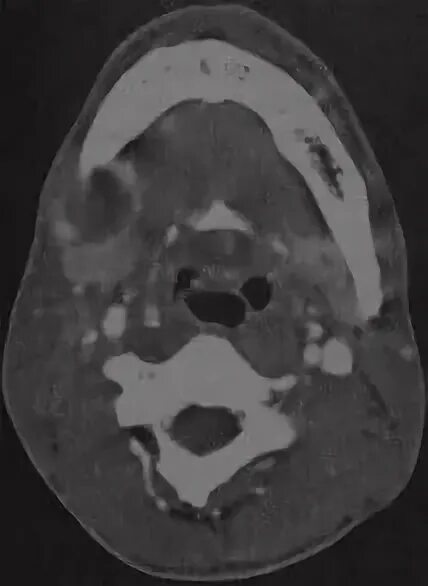

Абсцесс челюстного пространства